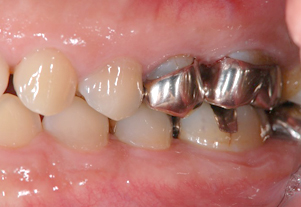

セラミッククラウン

昔詰めた銀歯のお色が気になる方や金属アレルギーが心配な方へ

透明で美しく変色しにくい素材をおすすめします。見た目が天然歯に近い素材なので、区別がつきにくく年数がたっても変色しにくいことが特徴です。